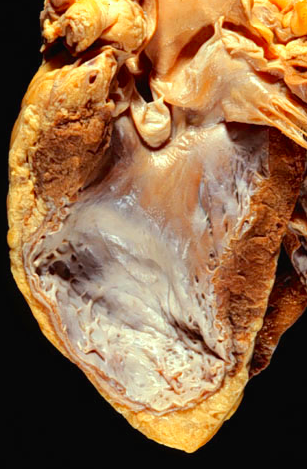

- Heart is opened to reveal the left ventricular free wall on the right and the septum in the center. There has been a remote myocardial infarction that extensively involved the anterior left ventricular free wall and septum

- The white appearance of the endocardial surface indicates the extensive scarring